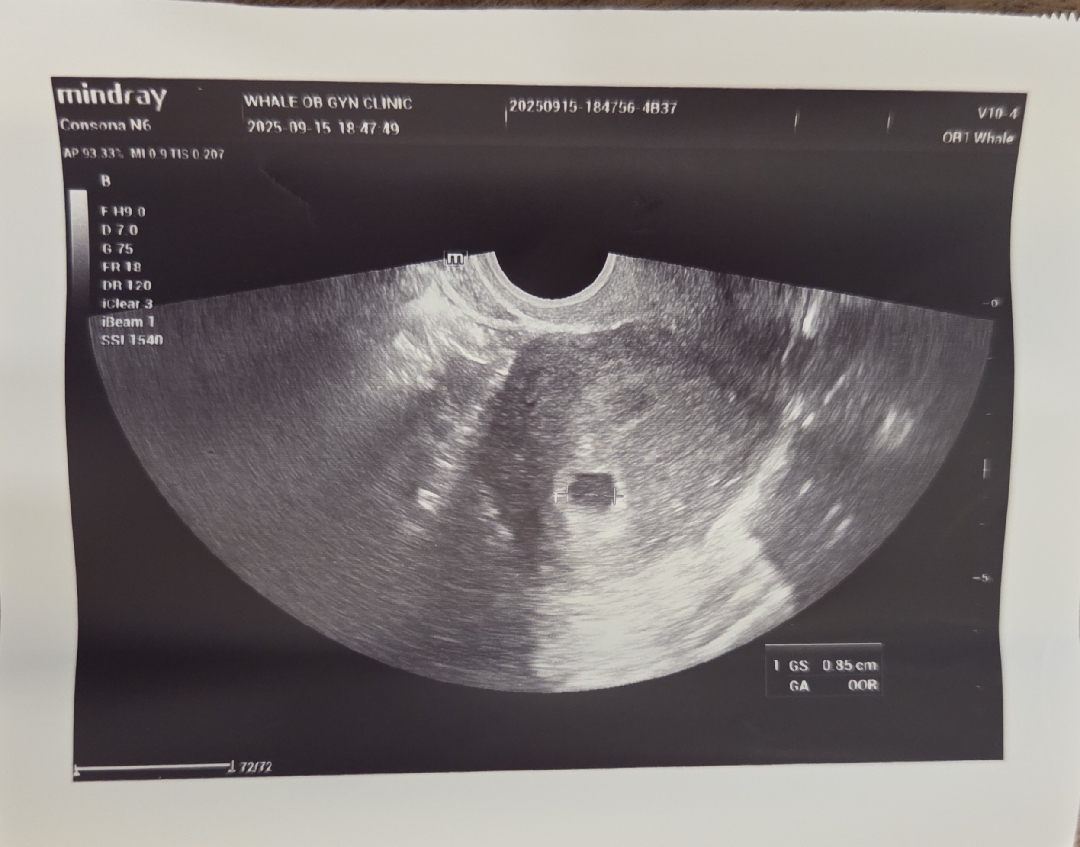

아가집 보고왔어요~~4주차

원래 이번주 금요일에 보러오라고 했는데.. 미리 보러 다녀왔는뎅.. 다행히 보여줬네용~ 우리 땡글이 집이에요~이모들 축하해주세요🩷